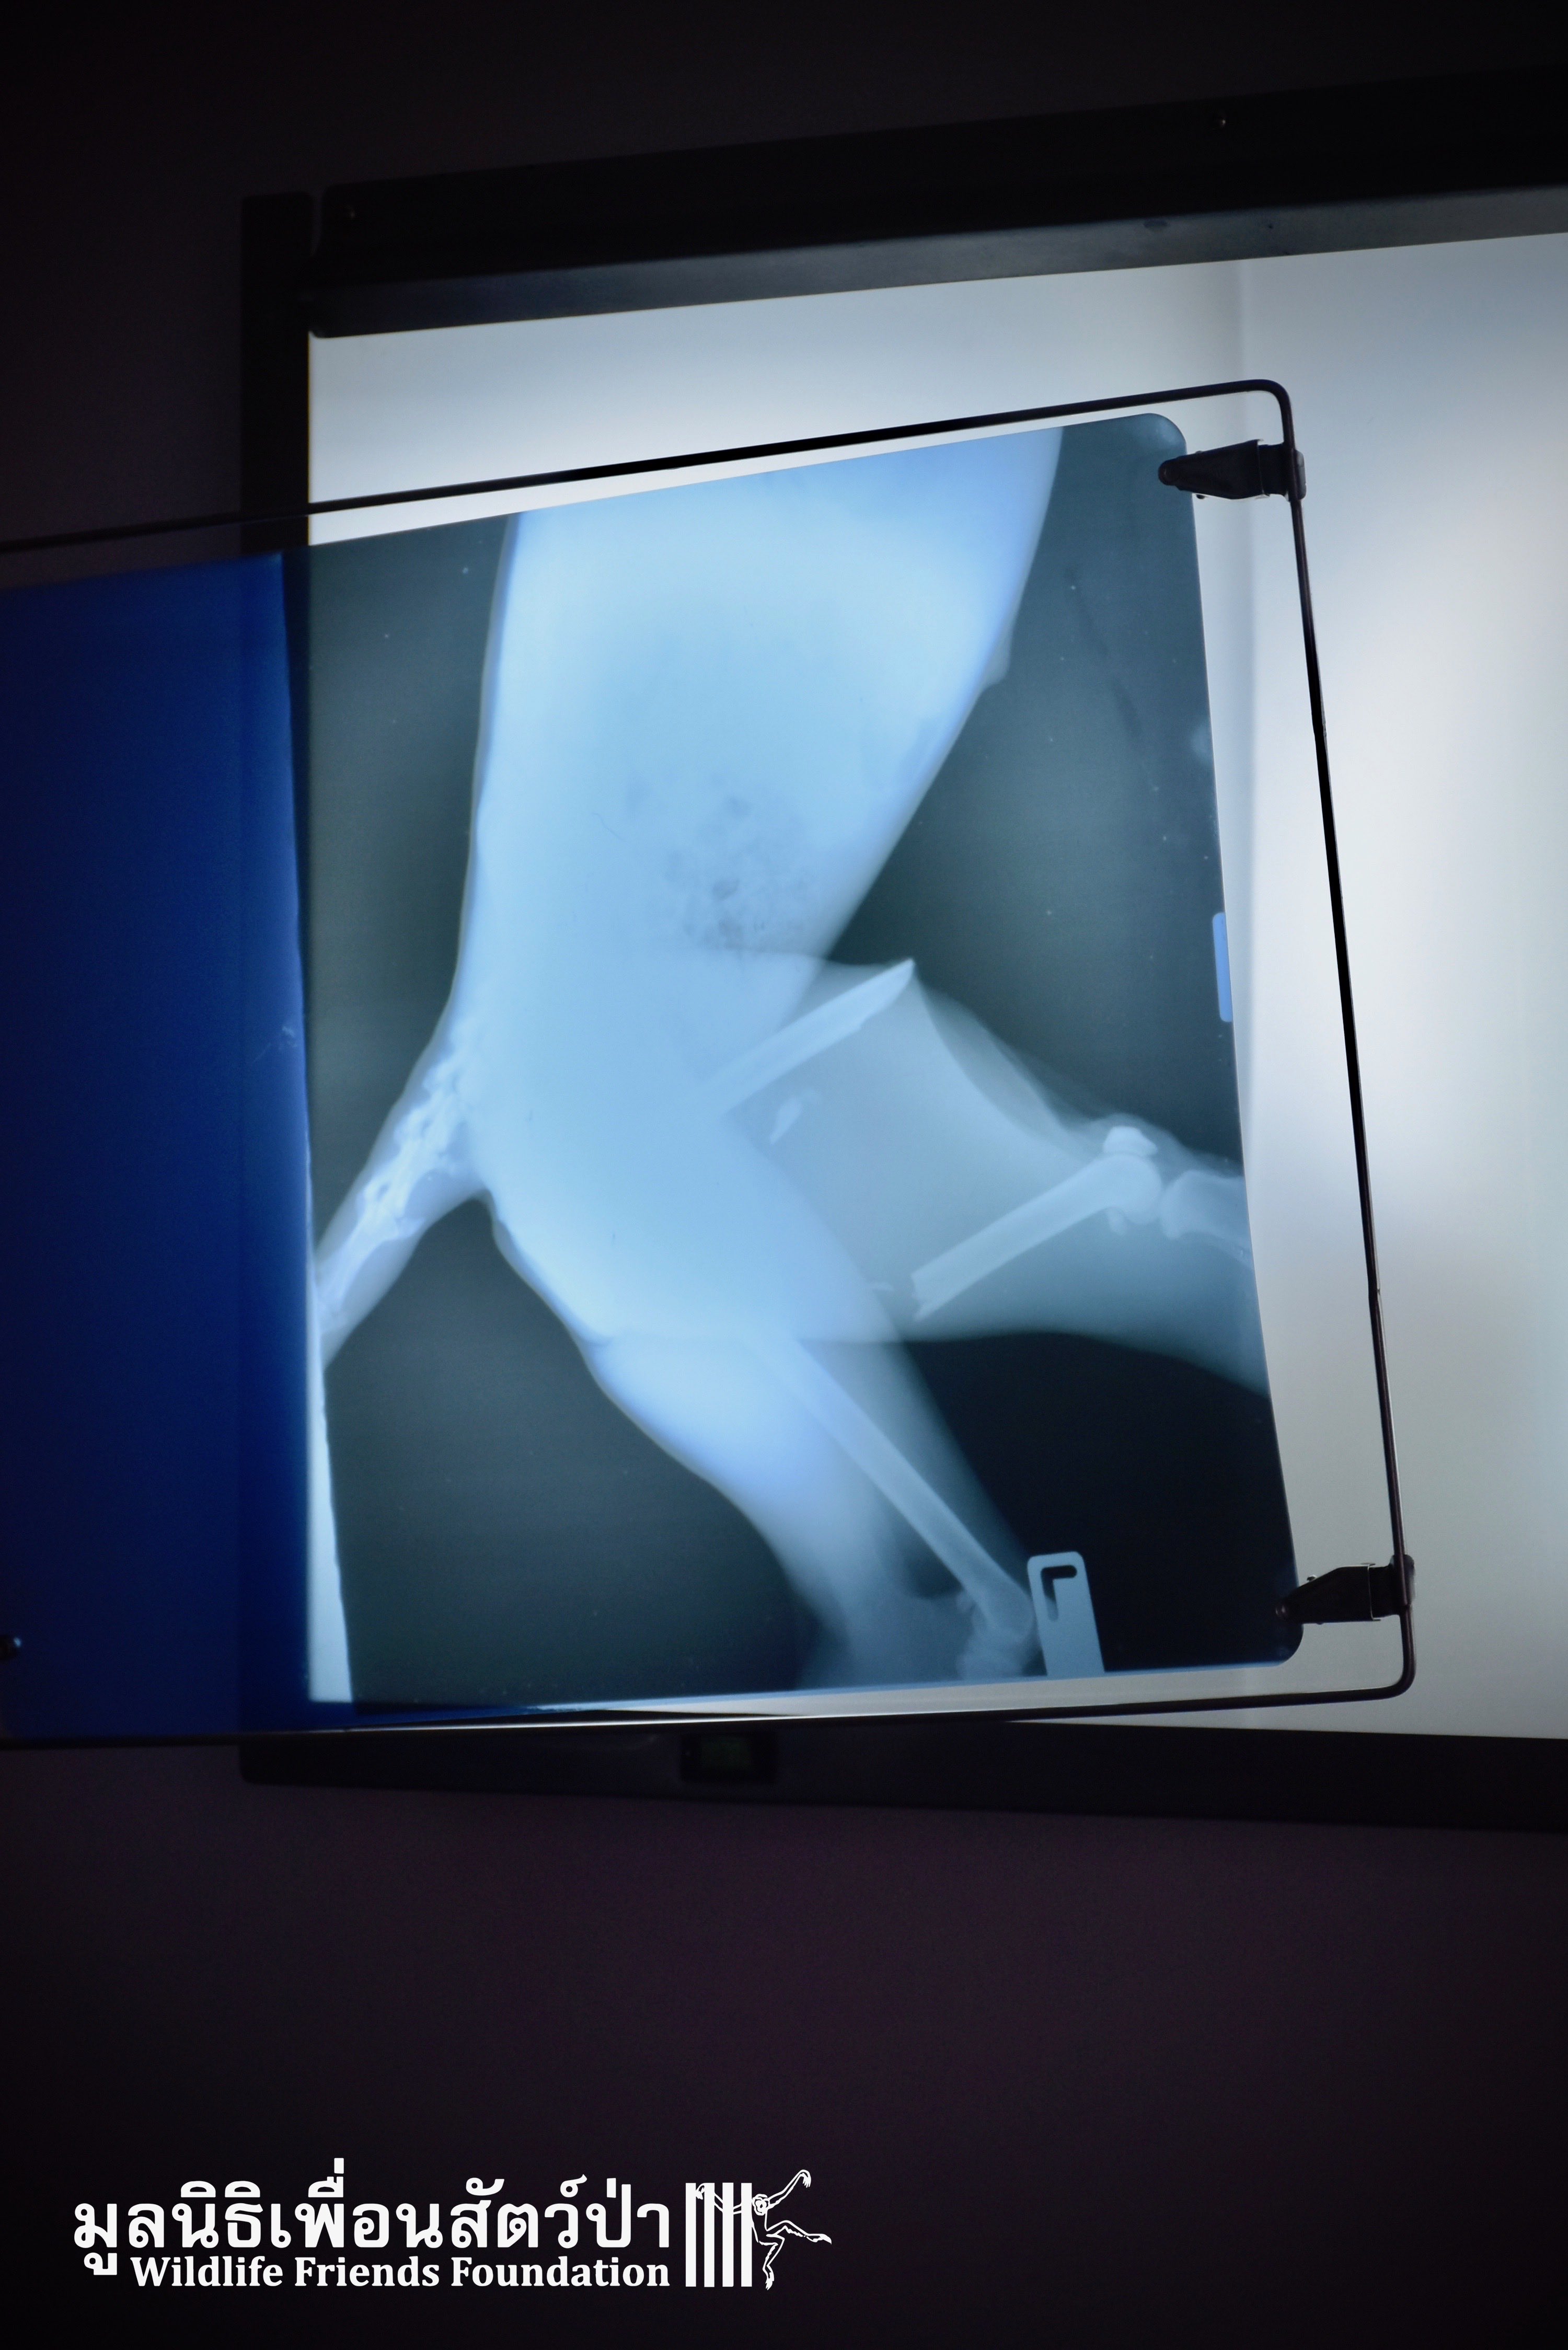

Last November we were called by a human rescue team who help an adult female dusky langur (Trachypithecus obscurus), who was injured on a road, after being hit by a car (see her full story of Rosy here: https://www.wfft.org/wildlife-general/wfft-wildlife-rescue-team-langur-distress/).

After successful restorative surgery and a recovery for a few months at the WFFT Wildlife Hospital, Rosy was finally ready to be released back to the wild! Early yesterday morning, she has been lightly sedated to avoid any excessive stress during transport, a 4-hour trip. The WFFT Rescue Team went to meet the people who rescued Rosy not far from the spot of the accident in order to be able to release her the closest to her previous home and suitable habitat, where her family and other troop members live. Once the transport crate opened, our friend didn’t need to be asked twice; she disappeared in less than 5 seconds in the great green expanse that was facing her. We wish her a long and happy life, away from any more troubles.